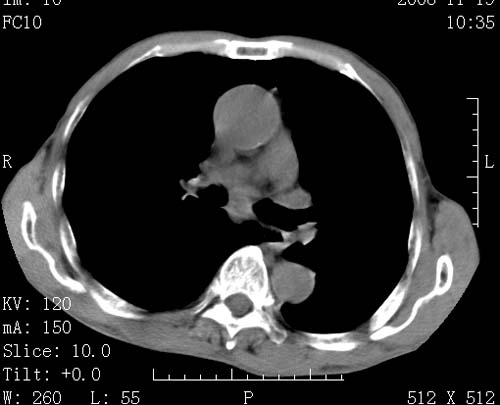

标题: CT16691:m 67 胃镜确诊食管下段及贲门癌 [打印本页]

标题: CT16691:m 67 胃镜确诊食管下段及贲门癌

术前查体,双肺部结节是转移?结核?请点评

转移 隆突下淋巴结亦肿大

首先考虑转移,纵隔内淋巴结亦肿大;

1)符合食管癌表现。2)两肺及纵隔淋巴结多发性转移瘤。3)左肺上叶舌段及两肺下叶炎症感染。

食管癌伴双肺转移,评述:肺部毛细血管网丰富,全身血液均快速流经肺部,癌细胞容易过滤定植,形成转移瘤,影象特点为以毛细血管末梢为中心的结节灶,边缘光滑锐利,少见有中心空洞着,不同来源的转移瘤可有各自特点,如甲状腺癌为双肺弥漫性微结节,本例有原发灶,双肺影象灶典型,左肺舌段条带状网格样伴胸膜天幕征,可视为癌性淋巴管炎。